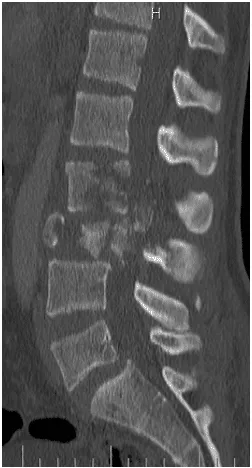

18 yo fell from 3 floors. Near complete loss of all neurological functions below the level of injury with near complete involvement of bowel and bladder

Patient was operated and the spinal canal cleaned up of all bony fragments. The spine was fixed from the side and the back to take care of instability.